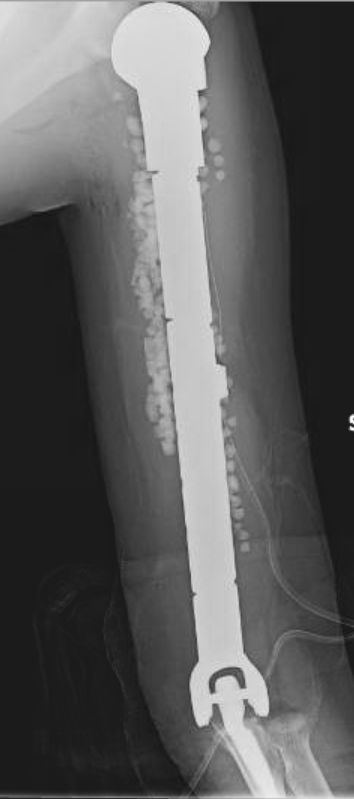

Maddie has been nothing but optimistic throughout the whole experience. She's completed three months of chemotherapy and had a major surgery. On April 28, 2017, her humerus bone was replaced with a titanium rod, as well as elbow and shoulder replacement. Maddie still has another 4-6 months of chemotherapy ahead.